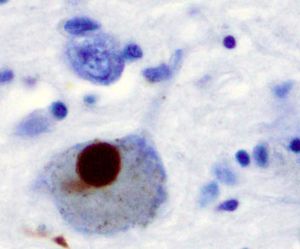

| 축적 형태 | 루이 소체 (Lewy bodies) 루이 신경돌기 (Lewy neurites) |

| 병리학적 특징 | 신경 세포 내 축적 및 응집체 형성 |

파킨슨병, 레비소체 치매, 다발성계통위축증과 같이 레비소체를 특징으로 하는 병적 상태에서 알파-시누클레인은 집합되어 불용성 원섬유를 형성한다.[212][213][93][94] 이러한 질환들은 시누클레인병증(synucleinopathies)으로 알려져 있다. 알파-시누클레인은 레비 소체 원섬유의 주요 구조골격 성분이다.[214] 때때로 레비 소체는 타우 단백질을 포함하지만,[214] 알파-시누클레인과 타우는 동일한 봉입체에 있는 두 개의 독특한 서브 세트 필라멘트를 구성한다.[215] 알파-시누클레인 병리는 알츠하이머병의 산발적인 경우와 가족력이 있는 경우 모두에서 발견된다.[216]

파킨슨병과 같이 레비소체를 특징으로 하는 병적 상태에서 알파-시누클레인(α-시누클레인)은 응집되어 불용성 원섬유를 형성한다.[212][213] 이러한 질환들을 시누클레오파티라고 한다. 알파-시누클레인은 레비 소체 원섬유의 주요 구조 성분이다.[93][94] 레비 소체는 때때로 타우 단백질을 포함하지만,[214] 알파-시누클레인과 타우는 동일한 봉입체에 있는 두 개의 독특한 서브 세트 필라멘트를 구성한다.[215] 알파-시누클레인 병리는 알츠하이머병의 산발적인 경우와 가족력이 있는 경우 모두에서 발견된다.[98]